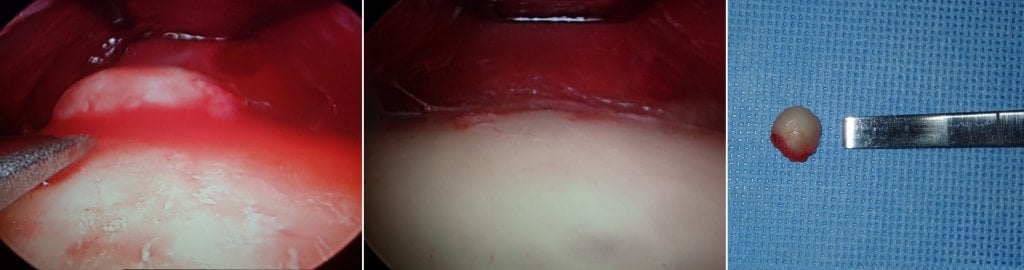

The treatment can frequently be performed with endoscopic technique through a button hole incision. It can be performed with local anesthesia, but due to the instrumentation required to remove the lump and smooth the bone, IV sedation is preferable.

The images below show selected before and after cases of endoscopic osteoma removal.

The above image shows the removed osteoma which is about the size of a small peach seed.